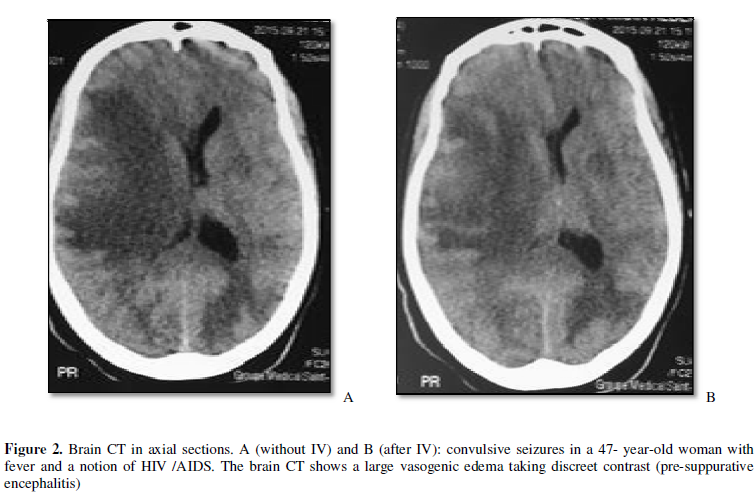

that may require an urgent neurosurgery intervention. Then, according to

Sempere et al. [9], another

acquisition should also be performed after injection of iodinated contrast

medium in HIV infected patients or patients with a history of cancer in order

to exclude an abscess or tumor.

The pathologies that we

highlighted in the CT exploration of seizures were dominated by

meningoencephalitis (20.7%). According Bouh et al. [8], causes of seizures seem to be influenced by the geographical

origin or level of development, with a predominance of infectious and vascular

causes in sub-Saharan Africa, while in the Western countries alcoholic and drug

causes seem more important. Indeed, Mbodj [12]